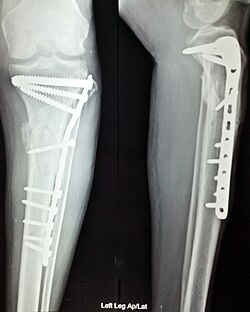

수술 후 내부 고정을 한 좌측 다리 골절의 전면 및 측면 X선 사진